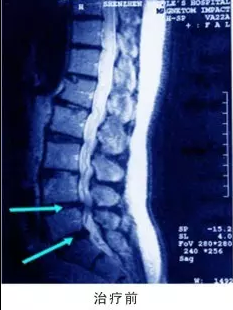

成年人椎间盘发生退行性改变,纤维环中的纤维变粗,变脆以致最后断裂,使椎间盘失去原有的弹性,不能担负原来承担的压力。在过度劳损,体位骤变,猛力动作或暴力撞击下,纤维环即可向外膨出,从而髓核也可经过破裂的纤维环的裂隙向外突出,这就是所谓的椎间盘突出。